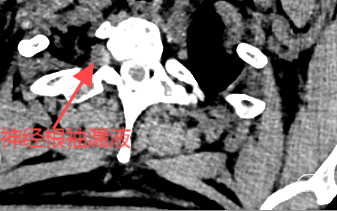

患儿仅15岁,因长期受此病困扰,沟通之后很快接受了脊髓造影,如下图:

明确瘘口之后,接受了T10-11靶向血贴治疗。